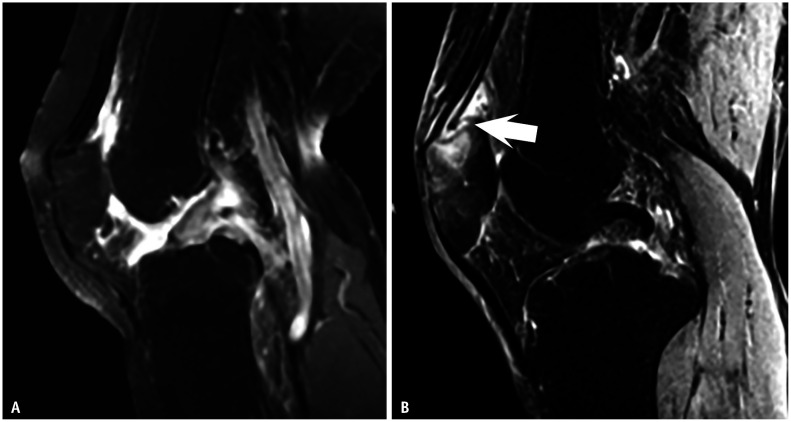

Differentiating rheumatoid arthritis (RA) and psoriatic arthritis (PsA) remains challenging, particularly when clinical and serological markers are inconclusive. Imaging provides critical insights, with MRI and dual-energy CT iodine maps highlighting key distinctions. Both conditions share inflammatory features such as capsular synovitis, tenosynovitis, and bone marrow edema. However, periarticular inflammation is often a strong indicator of PsA. This reflects their differing inflammatory targets: RA primarily involves the synovium, whereas PsA targets the enthesis. This distinction contributes to the broader bone marrow edema seen in PsA and explains inflammatory changes at the distal interphalangeal joint and dactylitis, which are characteristic of PsA but not RA. Recognizing these inflammatory patterns and distributions is essential for accurate diagnosis and treatment guidance.